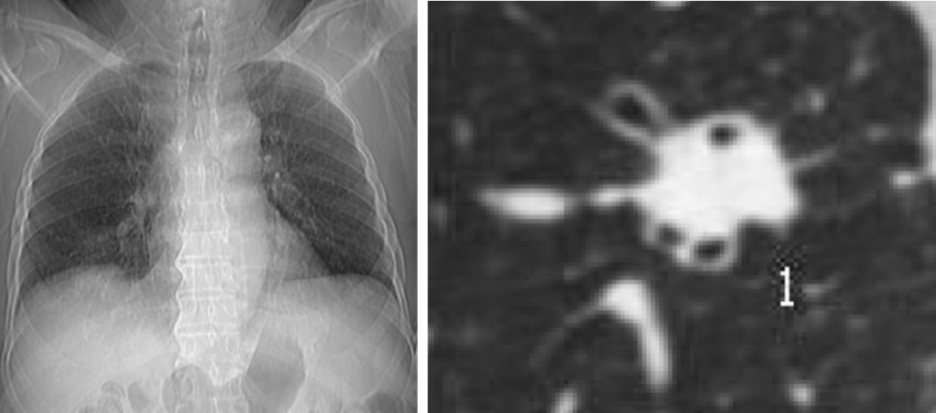

胸片(左图)看不见肺结节,CT(右图)清晰地显示肺结节,最后证实该结节为肺癌

而胸片仅能发现直径大于13 mm的肺结节,用胸片来发现早期肺癌,哪怕阅片经验丰富,水平很高的医生也难免漏诊肺内较小的病灶,“年年体检都正常,一发现肺癌就是晚期”的悲剧就易发生。